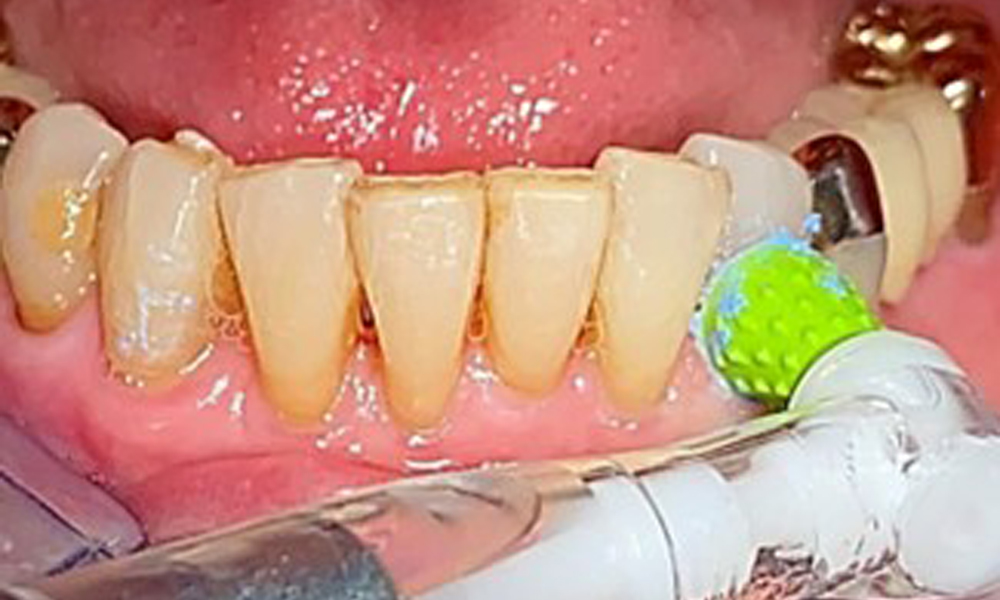

Die Patientin wurde vor über 25 Jahren mit einer kombinierten herausnehmbare Implantat-Teleskopprothese im Oberkiefer versorgt (Abb. 1, Abb. 2, Abb. 3) und ist sehr glücklich über ihren Zahnersatz. Im Unterkiefer hat die Patientin einen suffizienten festsitzenden Zahnersatz. (Abb. 4)

Die Patientin putzt 3× am Tag ihre Zähne und Implantate mit einer Handzahnbürste und einer Einbüschelbürste. Die Zahnzwischenräume pflegt die Patientin einmal täglich mit Interdentalbürstchen abends. Die Prothese putzt die Patientin nach jedem Essen.

Frontalansicht mit dem eingesetzten Zahnersatz im Oberkiefer.

Abb. 1: Frontalansicht mit dem eingesetzten Zahnersatz im Oberkiefer.

Eine Einbüschelbürste insbesondere für die Teleskope sind empfehlenswert (Abb. 8) und Interdentalbürstchen mit der passenden Größe sind der Patientin aufzuzeigen (Abb. 9). Die Patientin setzt diese Empfehlungen der häuslichen Mundhygiene seit vielen Jahren um und wird im Rahmen der unterstützenden professionellen Präventionssitzung bestärkt, dies weiterhin zu tun.

Darstellung einer Einbüschelbürste zur häuslichen Pflege für Implantate und Teleskope.

Abb. 8: Darstellung einer Einbüschelbürste zur häuslichen Pflege für Implantate und Teleskope.